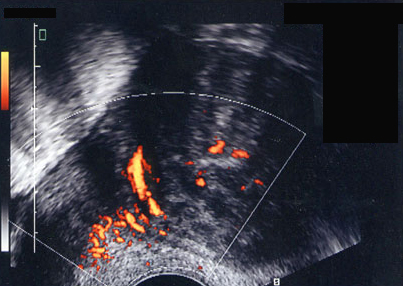

Fibrome utérin. Vascularisation encorbellante